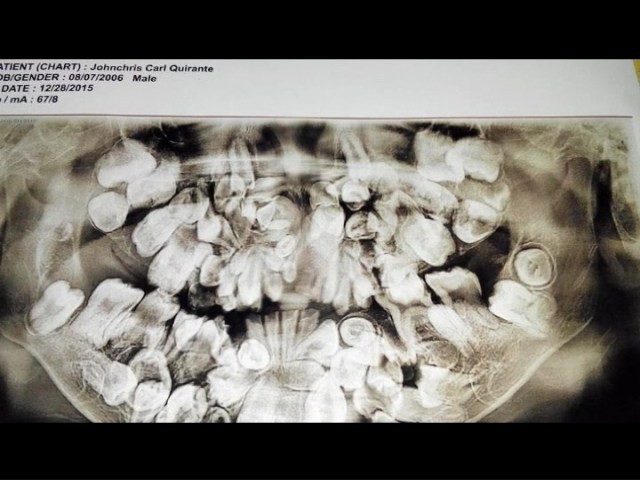

Johncris vừa được phẫu thuật nhổ 40 chiếc răng. Ca phẫu thuật đã thành công và sức khỏe cậu bé đang dần ổn định. Tuy nhiên, Johncris phải cần thêm 7 cuộc phẫu thuật nữa để có một hàm răng bình thường, dự kiến toàn bộ quá trình này mất khoảng 4 năm.

40 chiếc răng được nhổ sau cuộc phẫu thuật.